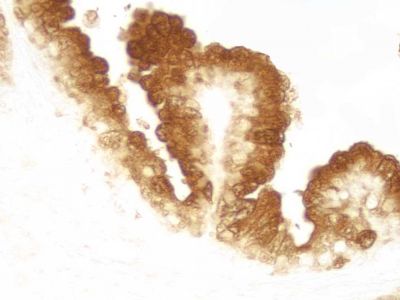

The ImmPRESS Polymer Reagents produce outstanding immunohistochemistry and immunocytochemistry results due to increased target accessibility, binding specificity, and signal intensity along with low background staining.

Staining Procedure

The staining procedure is simple as shown in the diagram below. Following a blocking step with the diluted normal horse serum, sections are incubated with primary antibody. After a brief wash, the appropriate ImmPRESS Reagent is added to the sections and incubated for 30 minutes. Sections are again rinsed and the slides are developed with the peroxidase substrate of choice.